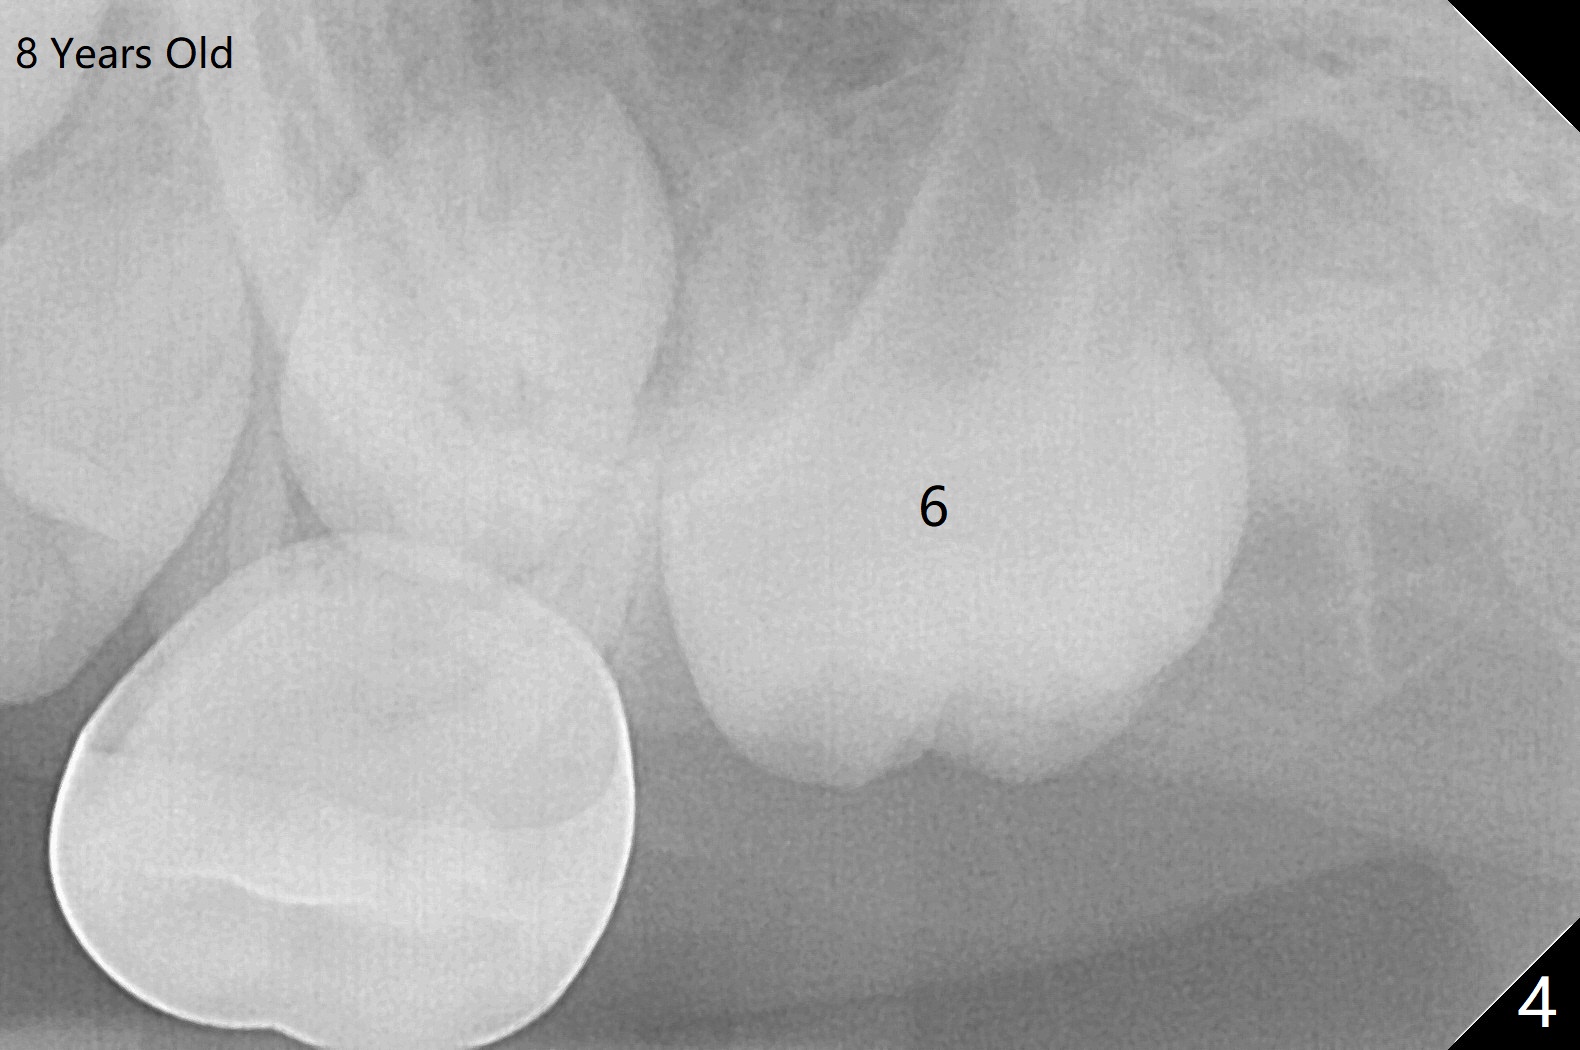

The upper left 1st permanent molar of a female remains unerupted between the age of 6 and 8 years old (Fig.1-4). The distal root of E is resorbed (Fig.3), which may be a reason of blockage. It appears that the upper left molars are underdeveloped, including 7. Or UL6 is congenitally missing? What is the treatment plan? Wait or surgery?

Yes Xin. Sit tight. It will be a while before that root development causes it to erupt.